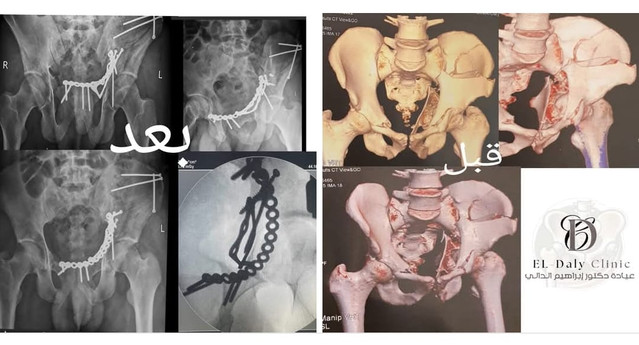

Pelvic Fracture Surgery

Advanced surgical treatment for complex pelvic and acetabular fractures using minimally invasive techniques and state-of-the-art fixation methods.

• Complex pelvic ring injuriesإصابات حلقة الحوض المعقدة

• Acetabular fracture reconstructionإعادة بناء كسور الأمبوت

• Minimally invasive surgical approachesالمداخل الجراحية غير المؤثرة

• Post-traumatic deformity correctionتصحيح تشوهات ما بعد الإصابة